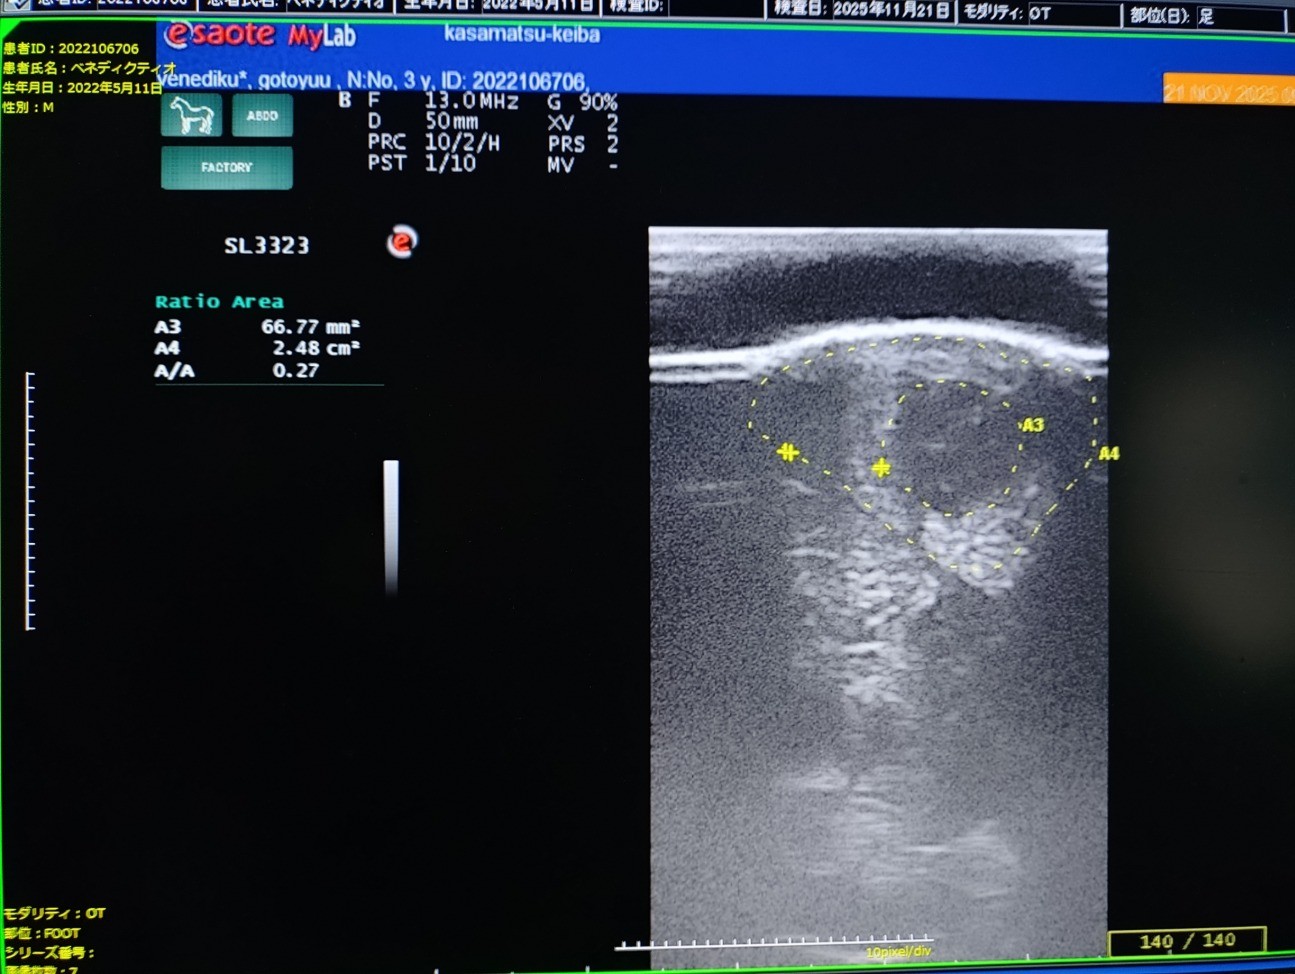

レース後に左前脚の浅屈腱炎発症が判明。損傷率はコア型の27%で全治にかなりの時間を要することからファンド解散となり、オークションへ出品いたしました。

18日のレース後、裏スジを腫らしていたのでエコー検査したところ、27%の損傷が確認されました。常歩の歩様は跛行を見せておりませんが、気持ち熱感はあります。惜しい競馬が続いており、初勝利までもう一歩という段階で無念です。(笠松競馬・後藤佑耶調教師)